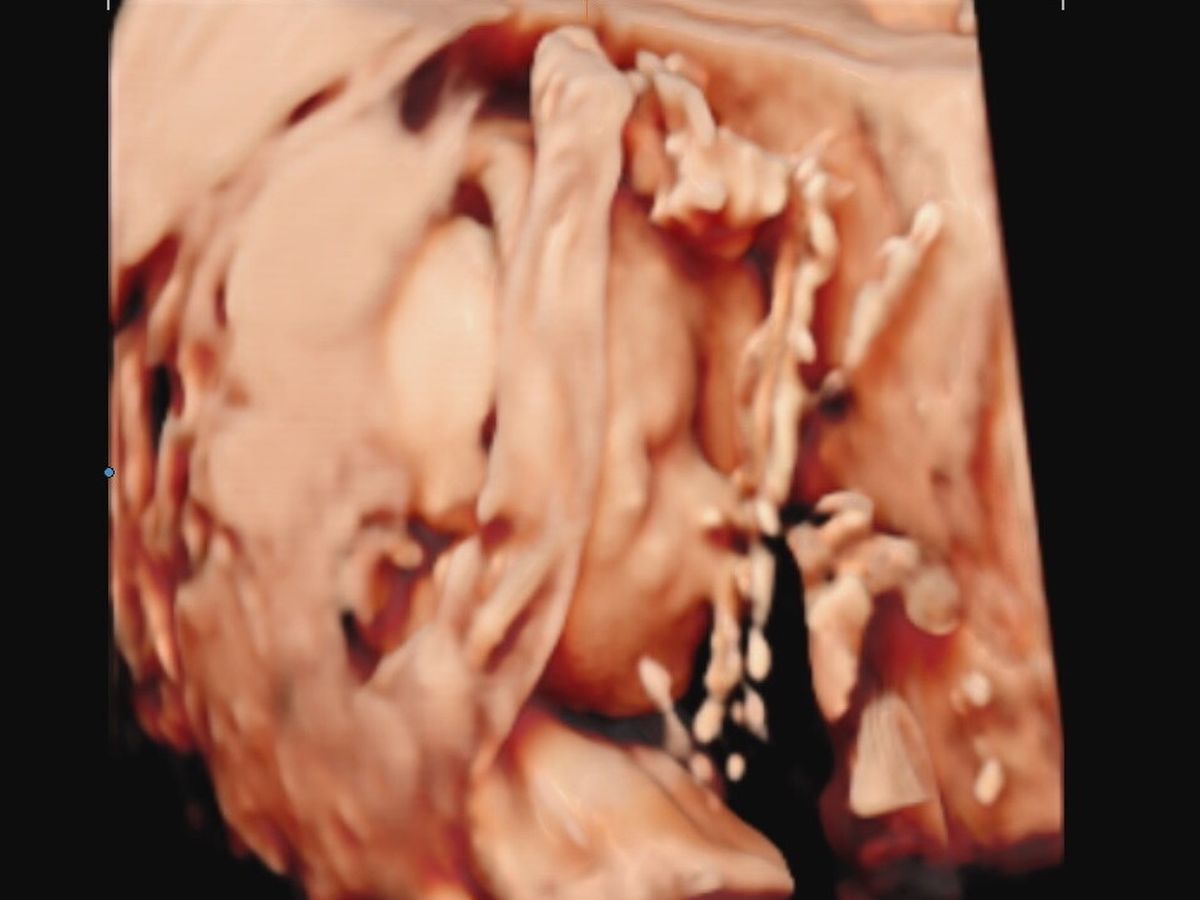

Main fundraiser photo

Unfortunately we received some not so great news at my anatomy scan for our baby girl this past week. They saw some things that didn’t look quite right so we were sent to Maternal Fetal Medicine where they confirmed a diagnosis of Spina Bifida. It is unfortunately a very severe case, common complication of spina bifida is called hydrocephalus, which leads to excess cerebrospinal fluid and pressure building up in the brain. It results from another condition called a Chiari 2 malformation, when part of the brain sinks into the upper spinal canal. Which is seen in the scans they did. The Dr thinks she may already have damage to the nerves in her legs but isn’t positive as they don’t test for that.